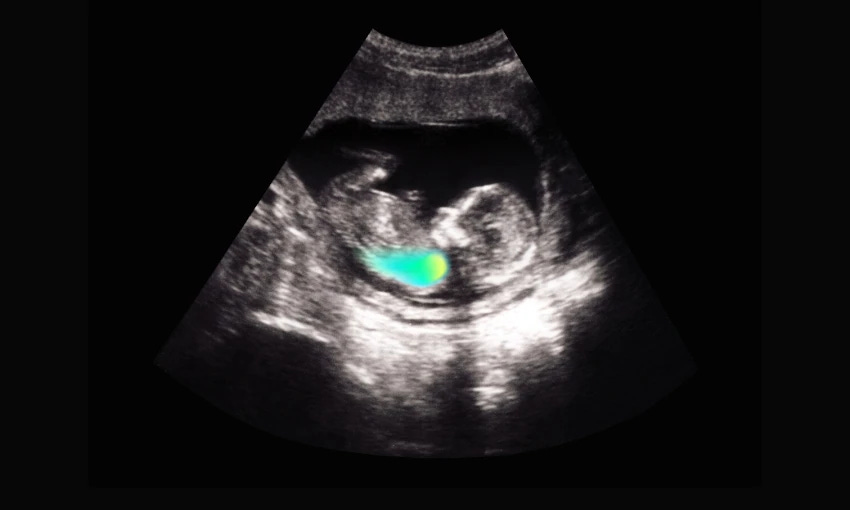

Ahiahi mārie, welcome to The Spinoff Daily. Today on The Spinoff: Has David Seymour ‘saved’ school lunches – or enshittified them? If the police call you while you’re driving, should you pick up? And why a sullen former All Black is the breakout star of this season of Celebrity Treasure Island. “Suddenly there were a lot of people in the room. They wanted to do a C-section, now. The doctors visibly relaxed when I agreed to it; I wasn’t going to make this difficult for them. They pumped more anaesthetic into my spine, via the epidural. In the operating theatre, I started shaking violently. My teeth were slamming together, over and over. I put my hand over my mouth and squeezed my jaw as tight as I could, trying to make it stop. I couldn’t see or feel what they were doing to my body. The sudden sound of a baby’s cry was shocking. He hadn’t been in the room, and now he was. I saw his back for a moment as someone carried him away, then I turned my head sideways and dry-heaved. Someone brought the baby back and lay him next to my head. I couldn’t stand the proximity; I felt so sick. They took him away again. After they stitched me up, I was wheeled to a different room, and my teeth stopped chattering. Abby came in, holding the baby, and lay him down next to me. She took a photo, the first photo ever taken of him: Elliott. In the picture, my skin looks green. Elliott is bright red, swaddled, massive. They wouldn’t discharge me till my heart rate went back down to normal. Nurses came in and measured it every hour, all day, all night, until it finally slowed four days later. Because of Covid, there were no visitors and I wasn’t allowed to leave the room – not that I could anyway, with a catheter in and every layer of muscle in my stomach sliced open. So it was just me and Elliott, alone together. He looked like Michael: big nose, sticky-out ears, hooded eyes. They were both strangers to me.” Has David Seymour ‘saved’ school lunches – or enshittified them? ‘It was quite baffling’: Police call driver on motorway to say ‘stop using your phone’ Who will miss Auckland Transport the most if it goes? The most anti-AT councillors Most people approve of compensating survivors of abuse in care We deserve to go to school without worrying the roof will fall on us How can everyone be part of the AI revolution?

The slow and painful process of falling in love with my son